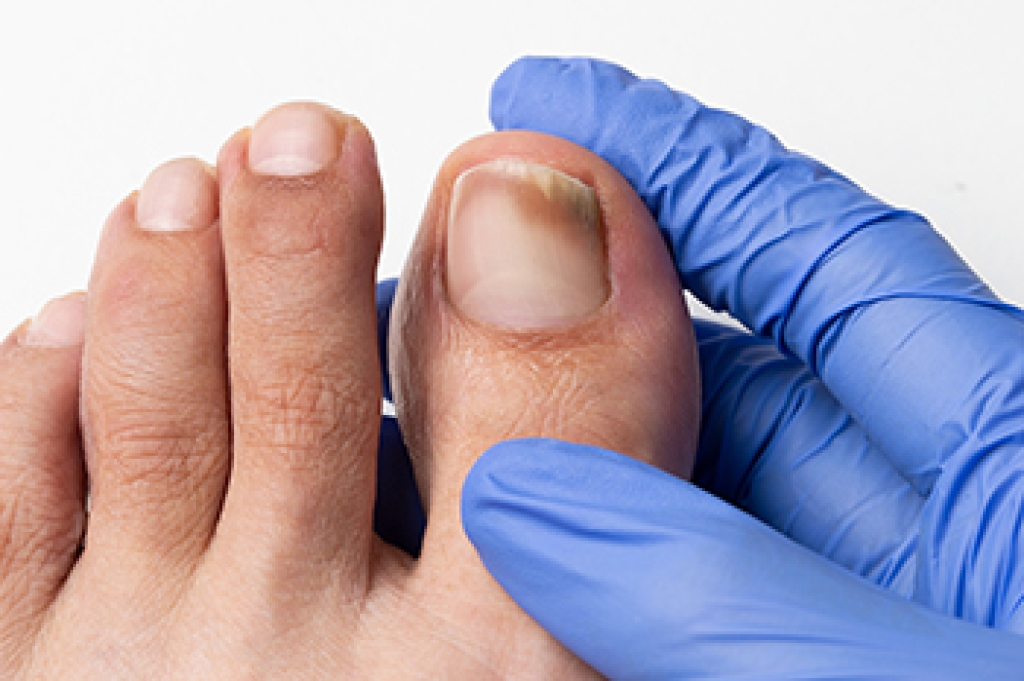

- Gouging toenails affecting nearby toe

- Shoes that don’t fit properly

Susceptible Infections

Diabetes and poor circulation can cause general loss of sensitivity over the years, turning a simple cut into a serious issue.